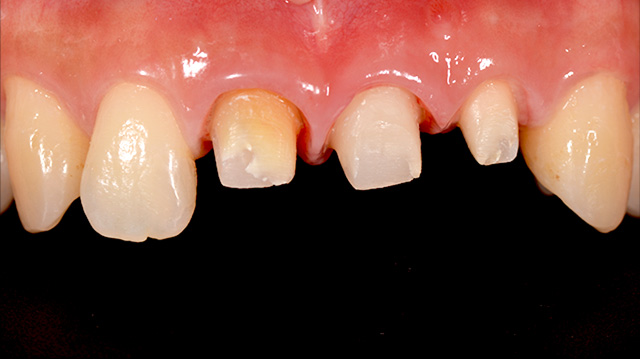

| 主訴 | 転倒して歯が割れた |

| 治療回数 | 3回 |

| 治療期間 | 約1ヶ月 |

| 費用 | 仮歯 5,500円 ジルコニアクラウン 176,000円 |